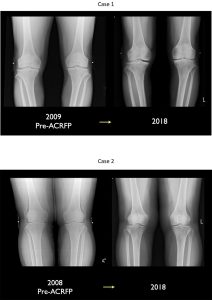

图3动脉再生辅助程序后软骨再生的辐射证据(ACRFP)。

Lyu及其同事在另一项研究中跟踪膝部OA三年后ACFP测试记录他们的膝部评分和膝部受伤和骨髓炎评分团队随后对这些分数进行了预处理和后处理比较结果表明91%的病人对治疗感到满意,即使是那些患有高级(四级)疾病的病人也是如此。确定KSS和KOOS分数后处理提高,显示症状解析和提高生活质量放射结果分析显示80%的病人回转软机变换(图3),而MRI结果研究显示72%的病人回转软机变换(图4)。